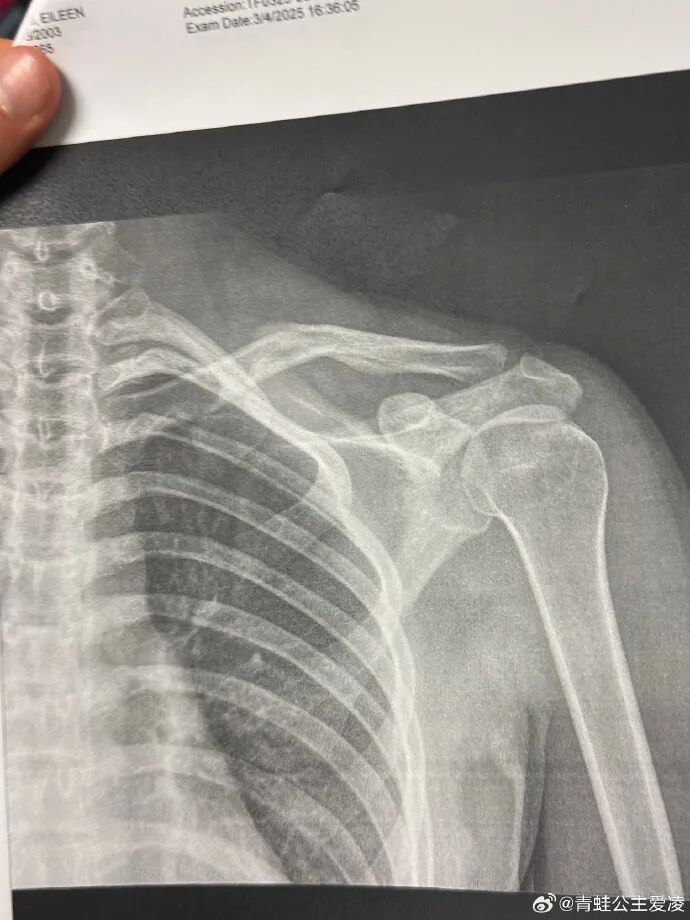

但事实是,谷爱凌确实在这个奥运周期的最后冲刺阶段不停经历着伤病的折磨。2025年3月9日,谷爱凌在社交网络上发布了一张X光片。图片上,她右侧锁骨的裂缝清晰可见,配文只有一个心碎的表情符号,而这仅仅是“职业生涯最艰难一年”的开始。